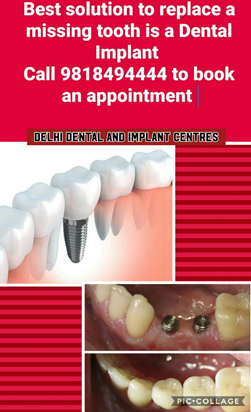

DENTAL IMPLANT

Q1. What Is Dental Implant?

Ans. Dental Implants Are Small Titanium Screw That Integrates With The Jaw Bone, Becoming The Foundation Of New Tooth Replacement.